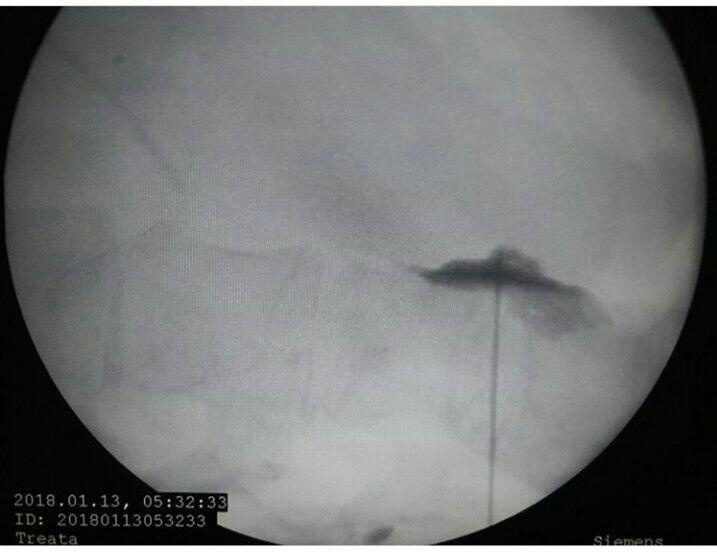

-لیزر(جراحی بسته) دیسک کمری

-اوزون تراپی دیسک بین مهره ای

-درمان تنگی کانال نخاعی غیرقابل جراحی

استفاده از روشهایی مانند تزریقات تخصصی (مانند اپیدورال، بلوک عصبی)، طب سوزنی، فیزیوتراپی، تحریک الکتریکی عصب و روشهای کم تهاجمی جراحی.